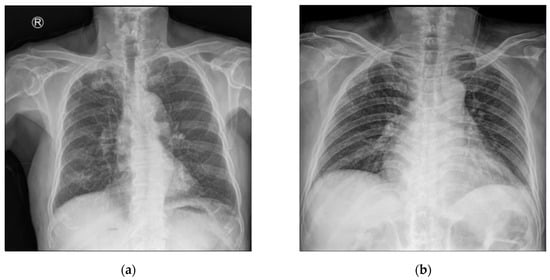

- Professional data collection and annotation conducted by experts at Cheonan Soonchunhyang Hospital, not on public datasets;